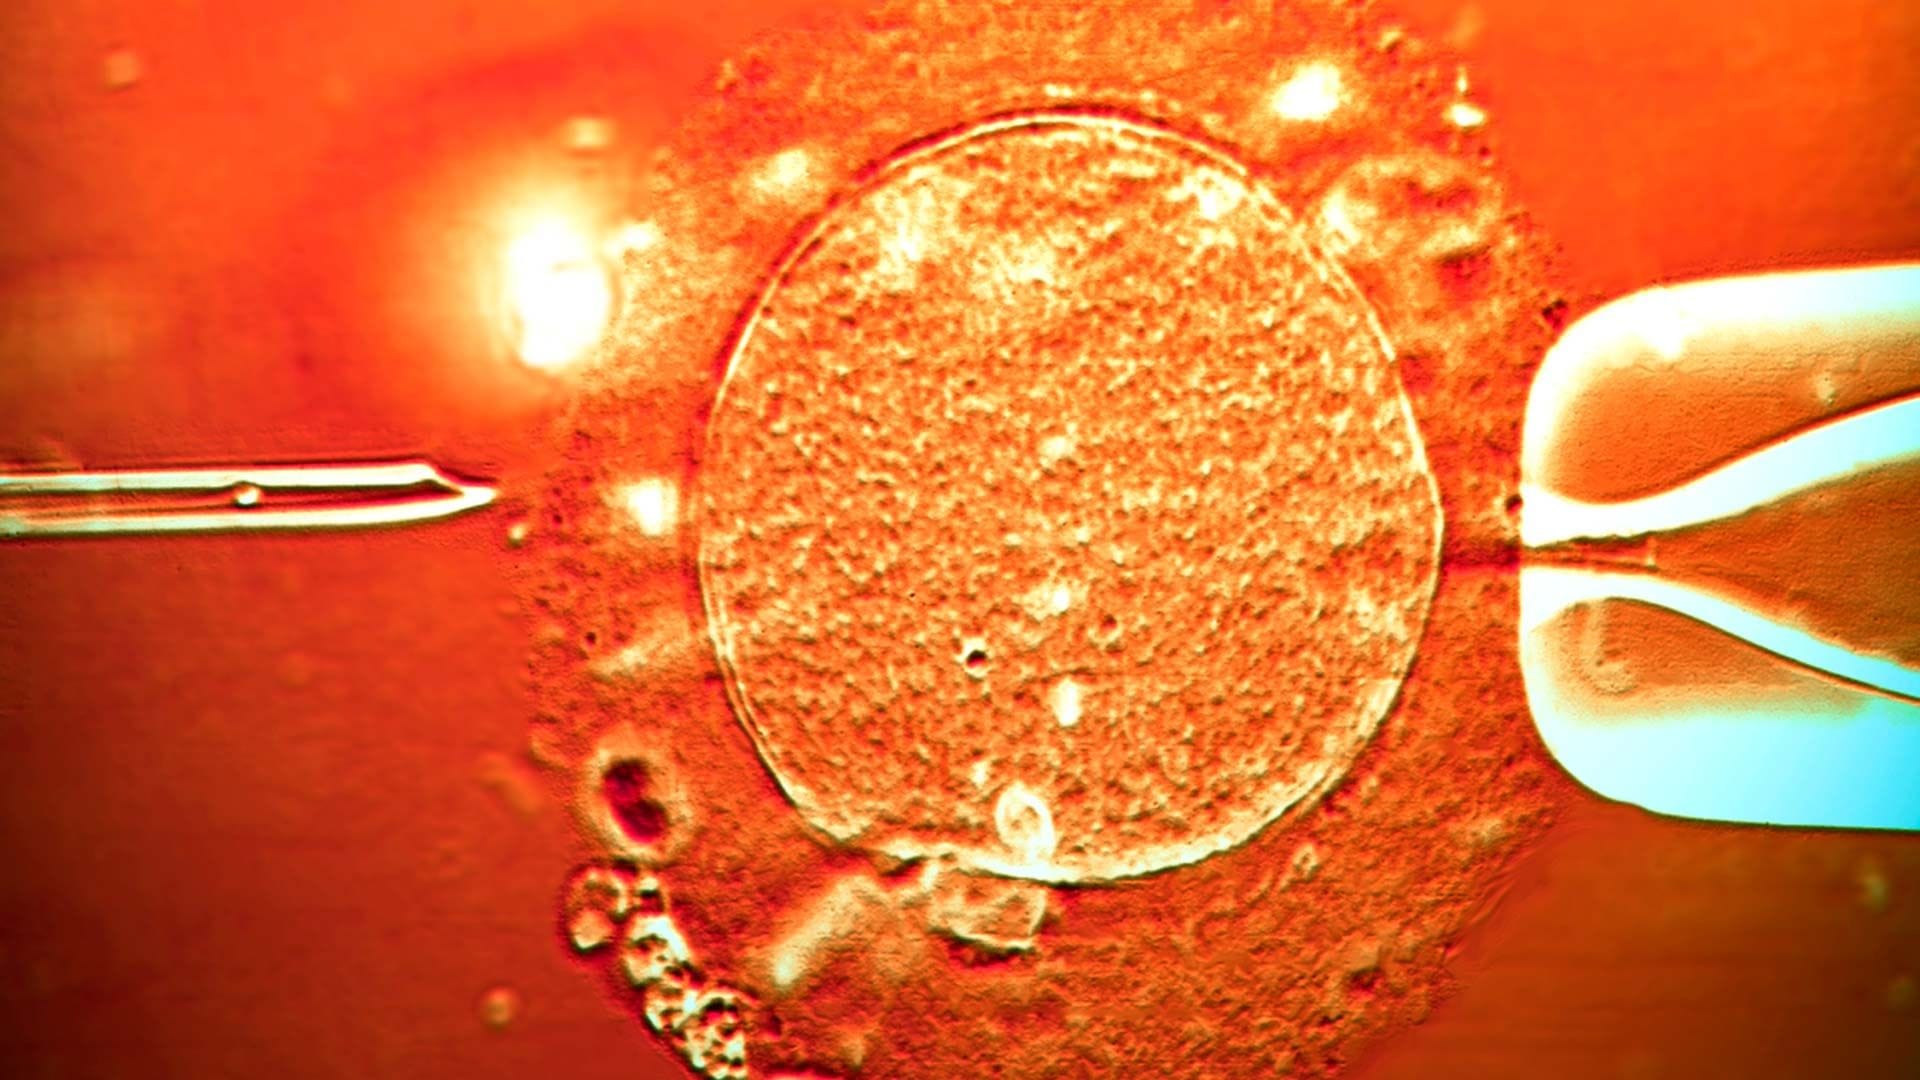

لێکۆڵینەوە لە سپێرمی ئەو بەخشەرەی کە بۆهێڵێکی کوشندەی بۆ 197 منداڵ گواستووەتەوە

بابەتێکی بنکۆڵکاری کە لەلایەن 14 دەزگای ڕاگەیاندنەوە کراوە، پەردە لەسەر یەکێک لە گەورەترین ئابڕووچوونە پزیشکییەکانی مێژووی ئەوروپا هەڵدەداتەوە؛ بەخشەرێکی تۆو (سپێرم)، بۆهێڵێکی کوشندەی بۆ 197 منداڵ لە 17 وڵات گواستووەتەوە.

چیرۆکی سەرەکی: پیاوێک کە بە کۆدی "7069" ناسێنراوە، لە ساڵی 2005ـەوە بۆ ماوەی 17 ساڵ تۆوی فرۆشتووە. خێزانەکان بەهۆی باشیی کوالێتییەکەیەوە "پارەی زیاتر"یان داوە، بەڵام دەرکەوتووە ناوبراو هەڵگری بازدانێکی بۆماوەیی شاراوە بووە لە بۆهێڵی (TP53). ئەمەش دەبێتە هۆی "کۆنیشانەی لی-فرۆمێنی" کە ئەگەری تووشبوون بە شێرپەنجە لە منداڵدا بۆ 90% زیاد دەکات.

ژمارەکان وا دەڵێن: لە کۆی سەرجەم ئەم منداڵانە، پشکنین بۆ 67یان کراوە، دەرکەوتووە بۆهێڵەکە بۆ 23 منداڵ گوازراوەتەوە. تا ئێستا 10 لەو منداڵانە تووشی شێرپەنجە بوون و چەند منداڵێکیش گیانیان لەدەستداوە.

پێویستە ئەمەش بزانیت: بازدانەکە تەنیا لە 20%ی تۆوەکانی پیاوەکەدا هەبووە، بۆیە لە پشکنینە سەرەتاییەکان نەدۆزرابۆوە. هەر منداڵێک لەو تۆوە پیسبووانە بێت، هەموو خانەیەکی جەستەی دەبێتە "بۆمبێکی تەوقیتکراو" و ئەگەری زۆرە تووشی شێرپەنجەی خوێن، مەمک و مێشک بێت.

لەلایەکی دیکەوە: ئێستا فرۆشتنی تۆوی "بەخشەری 7069" قەدەغە کراوە، بەڵام بانکی تۆو تەنیا بەشێک لە خێزانەکانی لەوە ئاگادار کردووەتەوە. ئەو خێزانانەش ژیانیان لێ بووەتە دۆزەخ و ناچارن مانگانە پشکنینی (MRI) و خوێن بۆ منداڵەکانیان بکەن و لە ترس و لەرزدا دەژین.